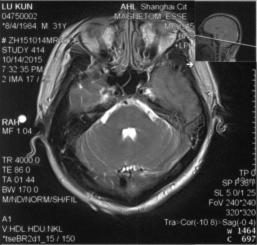

脑CT :左侧横窦条索征,左侧颞叶脑出血,见图1&5

图1